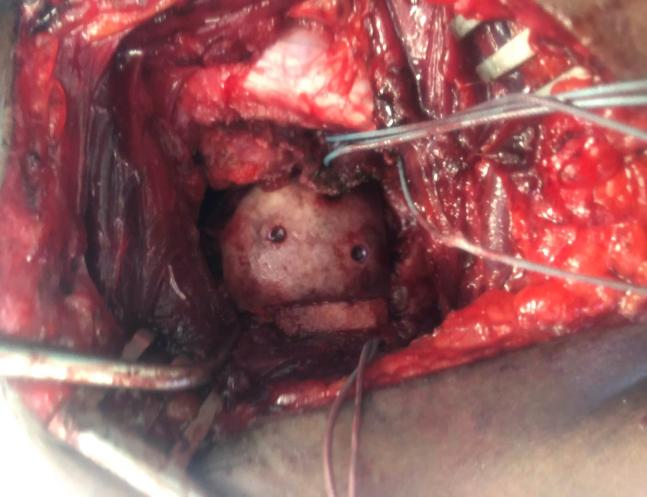

The utilization of computer planning and 3D-printed guide in the surgical management of a reverse Hill-Sachs lesion.

JSES Int. 2020 May 26;4(3):569-573. doi: 10.1016/j.jseint.2020.04.013. eCollection 2020 Sep.